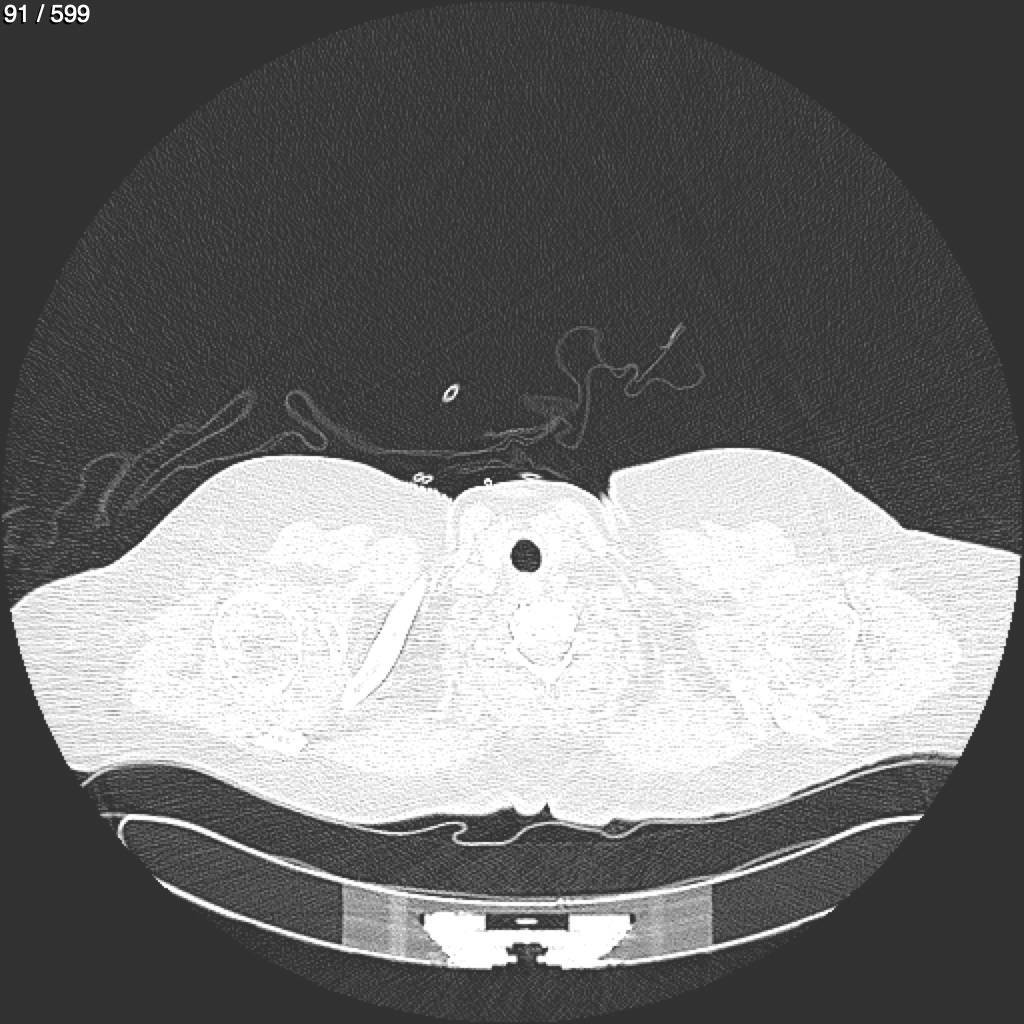

Home G​l​o​r​i​a​ ​G​l​a​d​y​s​ ​B​e​a​s​l​e​y​ ​-​ ​T​ó​r​a​x​ ​T​o​r​a​x​_​S​i​m​p​l​e​ ​(​A​d​u​l​t​o​)